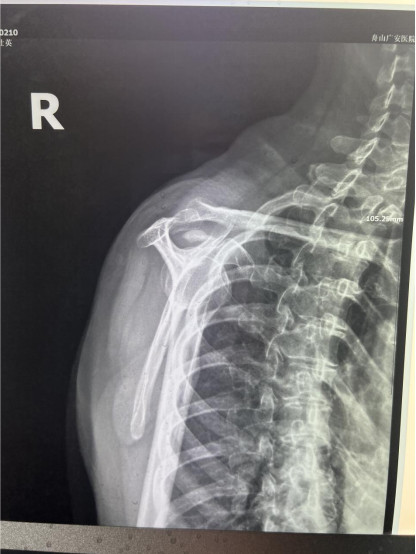

賀大媽慕名來廣安醫(yī)院找羅軍主任就診,面對羅醫(yī)生,賀大媽哭訴:“羅醫(yī)生,我真想剁下自己的這只胳膊。”羅軍主任根據(jù)患者的癥狀拍片,診斷為岡上肌鈣化性肌腱炎,隨后,羅醫(yī)生為李大媽進行了肩關(guān)節(jié)鏡微創(chuàng)手術(shù),竟從她的右肩“擠”出“牙膏”。

是不是只要病人撐得住,讓鈣鹽吸收就沒事了?羅軍主任表示,經(jīng)保守治療無法緩解或病程長的患者,應(yīng)盡早采取手術(shù)治療。而且,部分患者鈣鹽無法完全吸收,拖下去只會使病情惡化,造成肩膀肩袖肌腱的損傷。

羅軍主任表示,很多人會把肩痛都歸因于肩周炎,這是一個很大的誤區(qū)。其實,肩痛人群中只有15%左右是肩周炎,大部分肩膀疼痛由于肩袖損傷、肩峰撞擊征、鈣化性肌腱炎。而大多數(shù)人也因此認(rèn)為忍一忍就會自愈,常常延誤治療,關(guān)節(jié)鏡微創(chuàng)治療鈣化性肌腱炎,可以快速緩解疼痛,同時可以修復(fù)肩袖損傷,清理肩膀骨刺。